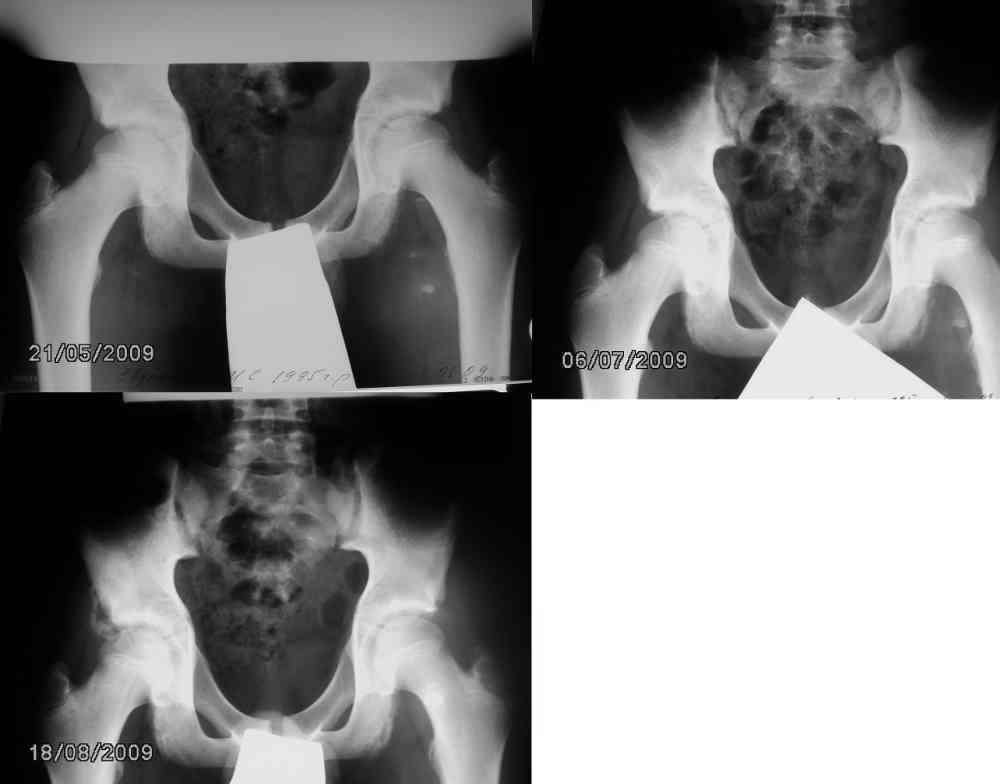

Первые жалобы год назад. Появились боли в левом бедре без ограничения

подвижности. В течении месяца боль мигрировала в область левого

седалищного бугра. На рентгенограмме костей таза от 21.05.09

нечеткость контура левого седалищного бугра. Идет диф диагноз между

новообразованием и остеохондропатией. На КТ данных за объёмный

процесс нет. Контрольный снимок через 1,5 мес от 06.07.09 признаки

формирования контура апофиза. Боли практически перестали беспокоить.

Следующий контрольный снимок 18.08.2009 – апофиз левого седалищного

бугра уже не вызывает особых беспокойств, но как объяснить появление

фрагментированного участка по латеральному контуру тела правой

седалищной кости. Вновь диф диагноз между новообразованием и

остеохондропатией (в середине июля был неубедительный факт травмы -

пнул мяч, появилась боль в правой паховой области). Клинические

проявления на момент проведения исследования скудные: незначительная

болезненность при напряжении мышц передней поверхности правого бедра.